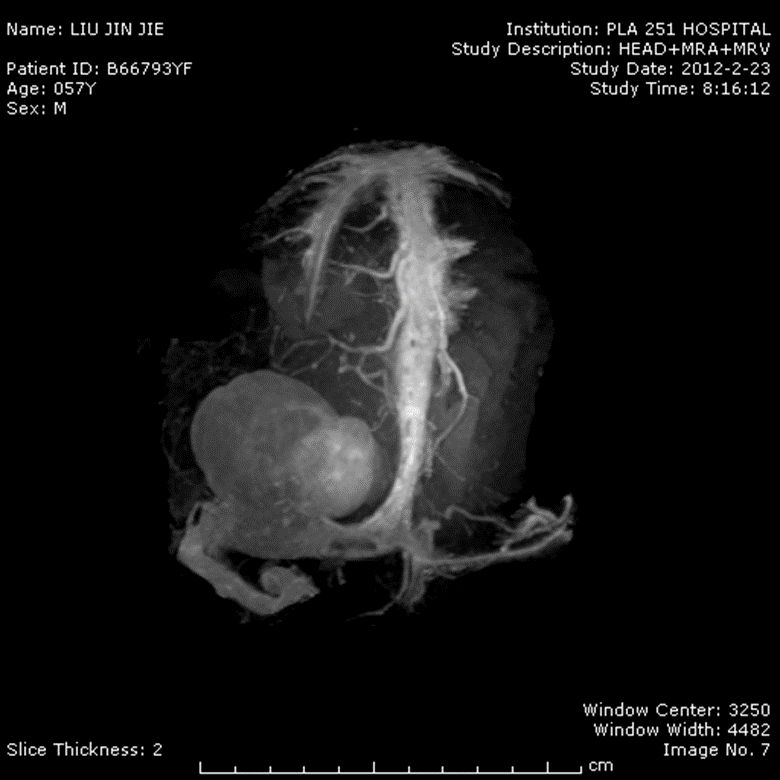

明胶海绵在神经外科手术是不可缺少的止血材料,对于静脉窦出血进行压迫止血、创面渗血贴敷这是我们常规止血方式,但是明胶海绵应用有更好的应用方式,下面介绍一个案例,这是一例基底部位于横窦的肿瘤,术中发现供血极为丰富的血管外皮肿瘤(如图所示),肿瘤突入到横窦内,而且此侧为主要引流静脉血通道,对侧横窦基本不发育,断窦切除肿瘤会造成严重后果,只能沿横窦切除肿瘤,但是单纯用电凝止血遇到前所未有的困难,肿瘤组织呈海绵状,只若是用电凝烧灼肿瘤组织,就可招来难以控制的出血,然而我们使用电凝镊夹持黄豆大小含水的明胶海绵,垫敷在肿瘤组织表面进行烧灼(功率15),结果止血效果非常奇特,就这样一个毫米的逐渐将肿瘤断离横窦。这个方法也可用于静脉窦小的裂隙出血,单纯压迫、或单纯电凝止血不满意的。有时候我们在分离动脉时,小的分支从主干贴壁断离,主干需要保留,你可使用电凝镊夹持含水的明胶海绵,大小根据裂孔或动脉主干所决定,功率为6,假如止血仍然不满意,你用临时动脉瘤夹进行阻断,然后重试,这里需要注意的是当夹持含水的海绵时先烧灼一下,使海绵与电凝镊略有粘连,不然会很容易被血冲走或被吸引器吸走。我把这种技术叫做“海绵电凝”技术,实际上与国内外采用的“不洁电凝”大致相同。